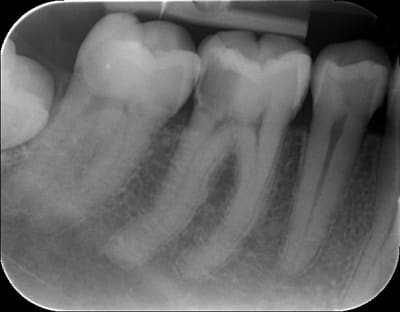

De belles cornes bien visibles, et c'était limite, ça saignait un peu, patient de 40 ans.

J'ai vu aujourd'hui à J+7 (dernière image), sensibilité modérée au froid, dureté d'un eugénate normal.